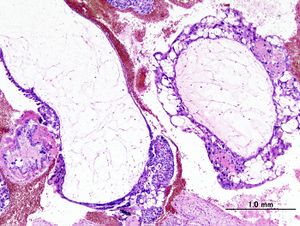

Histopathogic image of hydatidiform mole (complete type). H & E stain.

الحمل العنقودي هو حمل غير طبيعي، تظهر فيه محتويات الرحم على شكل حبات عنقود العنب ، ولذلك سمي بالحمل العنقودي، وفيه تتحول جذور أو شعيرات المشيمة إلى حويصلات منتفخة بالسوائل ويصبح شكلها العام مثل عناقيد العنب.